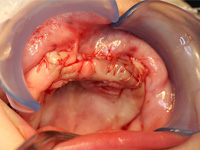

Excisional biopsy of the lesion was done under general anesthesia within hours of presentation. Fine-needle aspiration for fluid was negative. Sharp dissection of the lesion was followed by subperiosteal dissection, which revealed involvement of the vestibular and palatal cortices of the left maxillary alveolus. Both maxillary primary central incisors (erupted 61 and unerupted 51) and the unerupted left maxillary primary lateral incisor and canine (teeth 62 and 63) were excised with the lesion. Based on the clinical appearance of the tissues, the resected area was extended to include the presumed follicles of the maxillary permanent left central incisor, lateral incisor and canine (unerupted teeth 21, 22 and 23) to reduce the likelihood of the tumour's recurrence (Figs. 4, 5). Following resection, the soft tissue adjacent to the nasopalatine nerve was electrocauterized, and the surgical site was closed with a continuous vicryl suture (Fig. 6).